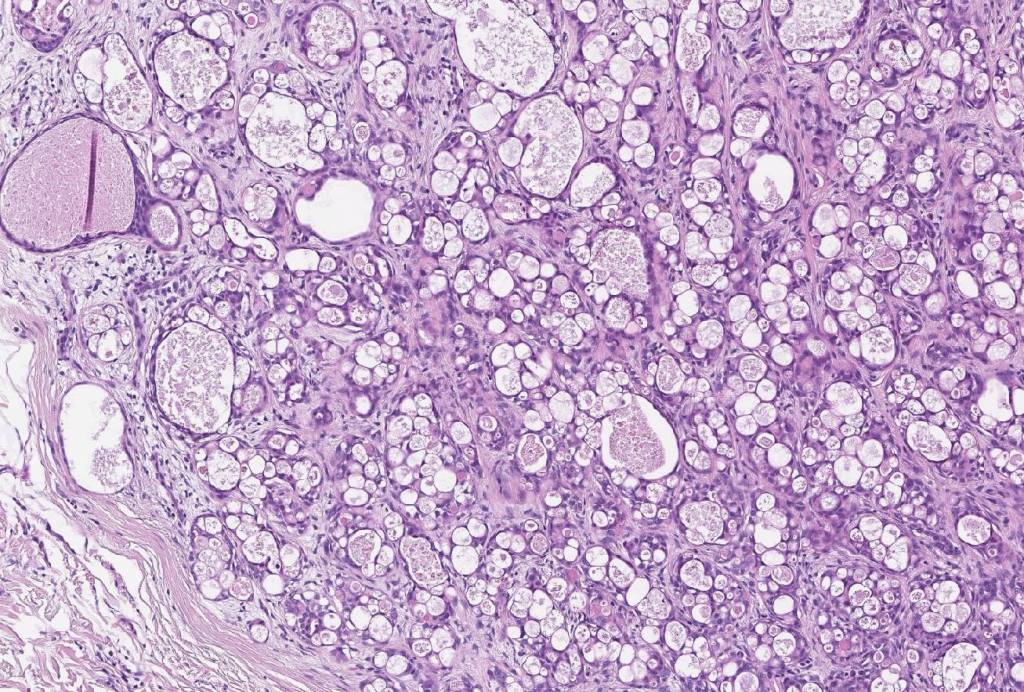

•Solid or cystic circumscribed or infiltrative dermal nodule

•Microcystic, tubular & solid patterns

•Vacuolated/granular/bubbly eosinophilic cytoplasm

•DPAS +ve luminal content

•Low grade atypia, mitoses very sparse, absence of perineural infiltration, lymphovascular invasion or necrosis